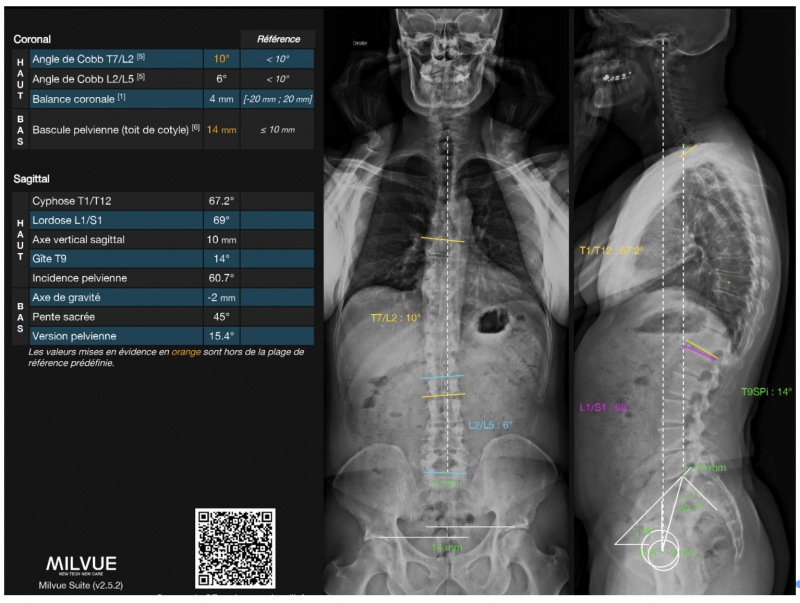

L’utilisation de l’EOS impose cependant quelques contraintes. L’acquisition dure entre 10 et 20 secondes (selon la taille du patient et la zone à explorer – rachis ou rachis et membres inférieurs) pendant lesquelles le patient doit rester immobile. Le volume de la cabine peut parfois limiter l’examen des sujets très corpulents ; enfin, la manipulation et la reconstruction nécessitent une formation spécifique du manipulateur.Au-delà de la question de la dose, la qualité géométrique est un autre atout majeur. L’orientation des faisceaux (orthogonaux entre eux et par rapport à la cible) évite les distorsions de projection. Les distances et les angles mesurés sur les clichés EOS sont directement exploitables : il n’est pas nécessaire de corriger les effets de magnification. La reconstruction 3D est toujours possible mais n’est pas systématique et nécessite une phase supplémentaire de post-traitement avec des outils dédiés, et n’est réalisée que dans certains cas particuliers, les reconstructions 2D étant généralement suffisantes dans la majorité des situations. L’aide d’outils d’intelligence artificielle a significativement simplifié la tâche du manipulateur, puisque les mesures automatiques ou semi-automatiques sont désormais accessibles avec la plupart des outils d’IA que les radiologues ont à disposition (mais impliquent un surcoût). L’IA permet également des mesures reproductibles, et rappelle systématiquement les normes angulaires pour chaque mesure, rendant l’analyse plus aisée pour tout le monde.Figure 3: Exemple de mesures automatiques réalisées à l’aide d’un algorithme d’Intelligence Artificielle.

L’un des principes fondateurs de l’EOS est la possibilité de relier, sur une même image, la statique rachidienne, la position du bassin et les axes des membres inférieurs. L’examen devient ainsi un outil d’analyse biomécanique globale.Figure 4: Exemple de livret résumé réalisé à l’aide d’un algorithme d’Intelligence Artificielle (correspondant aux mesures en Figure 3).